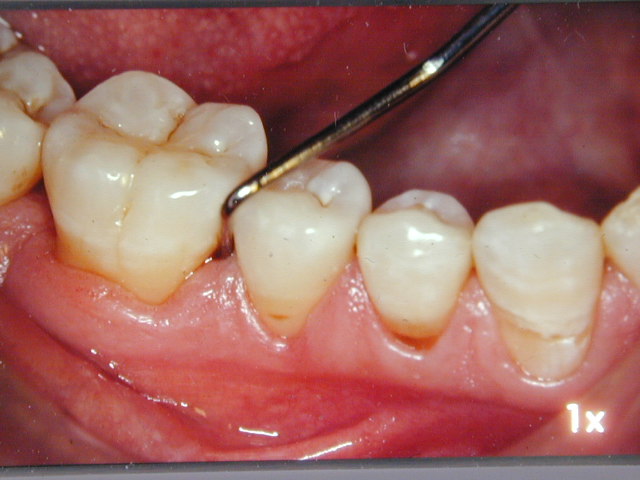

- Eemaldada bakteriaalsed ladestused igemete pealt ja igemete alt

- Vähendada igemetaskute sügavust ning hammaste arvu, mille ümber on igemetaskud >4 mm

- Mitte-kirurgiline parodontiidi ravi